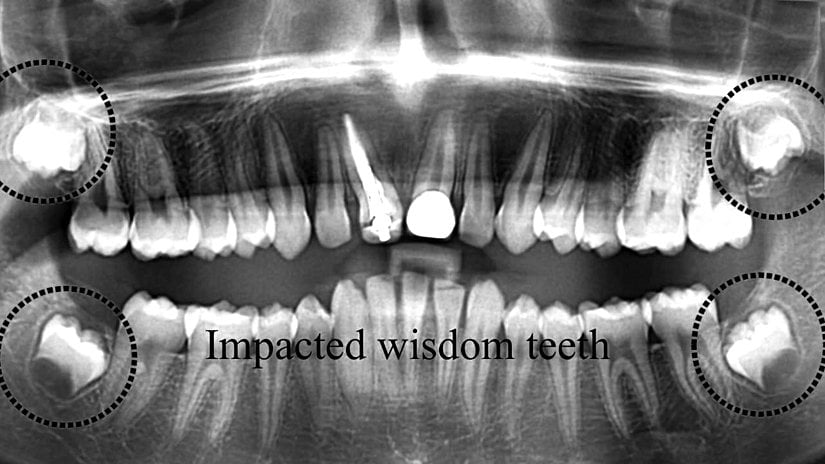

Yirmi yaş dişlerinin sıklıkla gömülü kalırlar, çıktıkları zaman doğru şekilde çıkmazlar ve diğer dişlere sürtünerek onların yapısını bozabilirler. Bu nedenle de ağrı ve enfeksiyona neden oldukları bilinmektedir. Bunun haricinde ise hiçbir işlevleri bulunmamaktadır. Dolayısıyla ağrıya neden oldukları zaman, diş hekimleri tarafından çekilerek hasta rahatlatılabilmektedir. 20 yaş dişleri çekilen kişilerin ağız fonksiyonlarında hiçbir azalma olmamaktadır. Aşağıda bu dişleri görmektesiniz:

Uzun yıllar insanlar bu dişlerin en başından neden var olduğunu anlayamamış ve bir çeşit "lanet" olarak görmüşlerdir; zira 20 yaş dişlerinin çıkmaya başlamasından çekilene kadar verdiği acıyı, bu dişleri sorunlu olarak çıkan kişiler gayet iyi bilirler. Ancak evrimsel biyolojinin gelişimiyle birlikte öncelikle insan evrimine ışık tutulmuş, daha sonra da bu tip körelmiş organların varlığı açıklanmıştır. 20 yaş dişleri de, insanda görülen 40'tan fazla körelmiş organ ve yapıdan sadece birisidir. Aşağıda, bu körelmiş yapıların ne şekilde hatalı oluşabileceklerine örnekler görülmektedir: